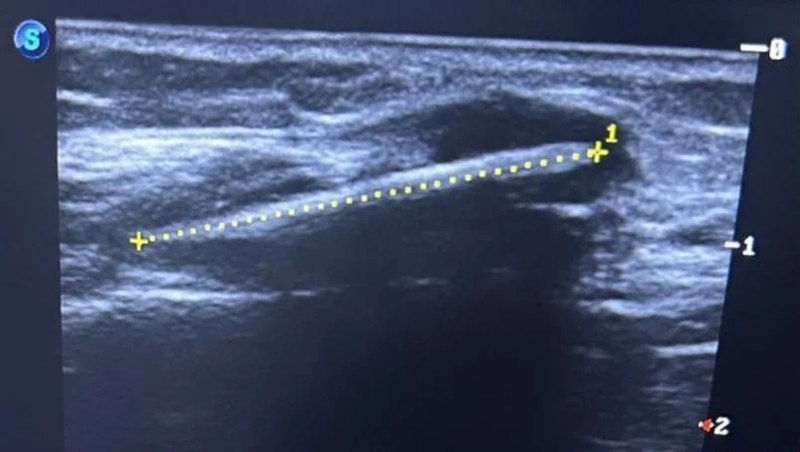

ผลการเอกซเรย์พบสิ่งที่น่าตกใจ เมื่อมีวัตถุแปลกปลอมปักอยู่ในเนื้อเยื่ออ่อนด้านนอกของกระดูกน่องขวา หลังจากสอบถามประวัติพบว่า เธอจำได้ว่าเมื่อ 16 ปีก่อน ขณะที่ออกไปเล่นข้างนอกเธอถูกไม้ไผ่แทงที่ขาขวา แต่ด้วยตอนนั้นบาดแผลมีขนาดเล็กและเลือดออกไม่มาก ทางครอบครัวจึงไม่ได้พาเธอไปรักษาอย่างจริงจัง ผลก็คือ ไม้ไผ่นั้นแอบอยู่ในร่างกายของเธอมาตลอดจนถึงปัจจุบันโดยที่เธอคาดไม่ถึง